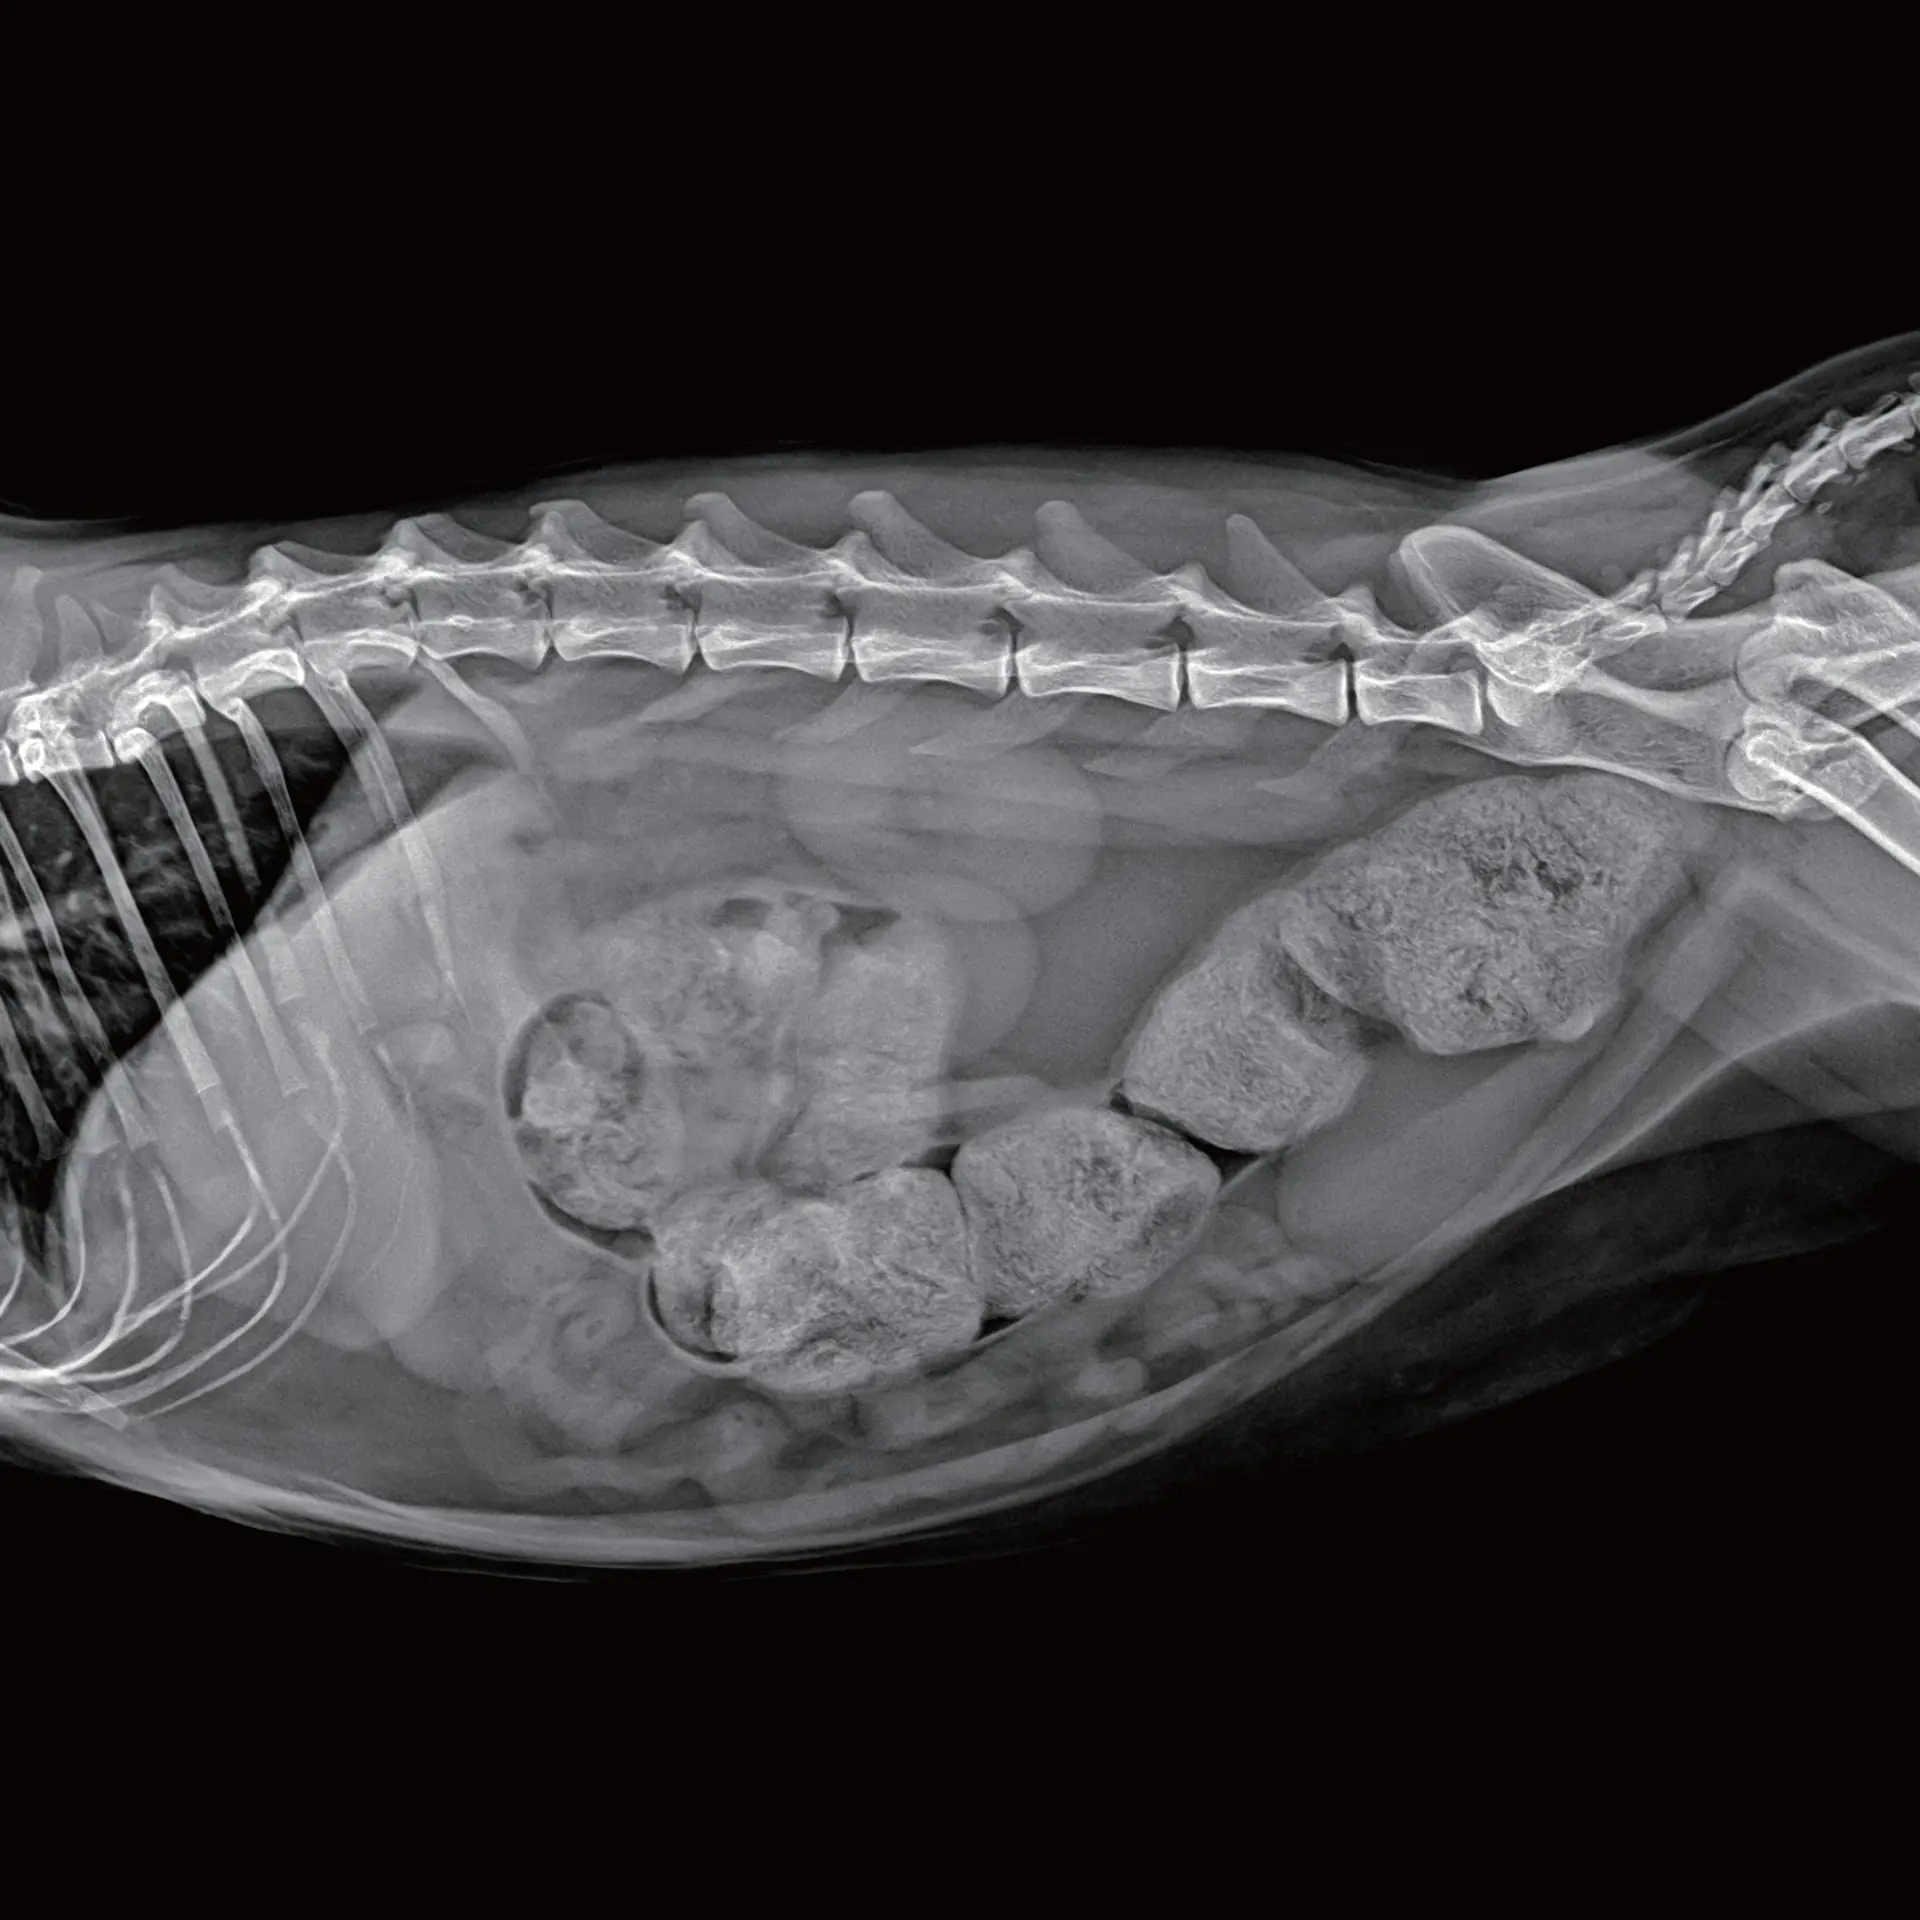

Abdominal Görüntüleme